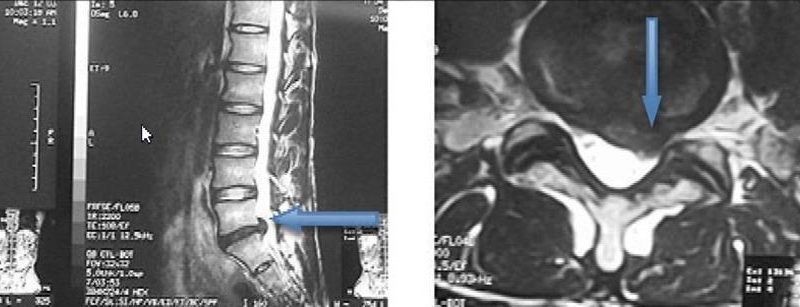

Estenose de Canal

A Estenose é uma doença degenerativa da coluna vertebral que consiste no estreitamento do espaço do canal vertebral. Na coluna cervical e na dorsal, a estenose pode causar compressão medular, associada ou não à compressão radicular. Na coluna lombar, pode causar compressão de uma ou mais raízes da cauda equina. A Estenose pode ser congênita ou adquirida. A forma congênita geralmente ocorre mais precocemente, já a adquirida pode resultar de doenças degenerativas, de outras doenças (como a doença de Paget) ou de traumas da coluna. Enquanto para algumas pessoas a Estenose pode ser assintomática, para outras pode provocar incapacidade de andar. Os sintomas mais comuns são dores nas costas, nádegas e pernas. Também podem ocorrer dormência e fraquezas nas extremidades inferiores.